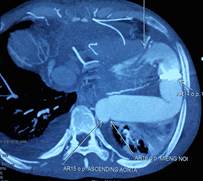

Hình 5: Kết quả chụp MSCT sau mổ

Khó khăn lớn nhất gặp phải khi thực hiện phẫu thuật cho bệnh nhân là không có vật liệu tiêu chuẩn để làm cầu nối. Đó là bộ vật liệu bao gồm ống nối cho mỏm tim, van tim nhân tạo và ống mạch nhân tạo. Các vật liệu này được thiết kế riêng cho phù hợp với việc luồn vào mỏm thất trái và đường đi của nó đến động mạch chủ xuống để không làm hẹp các miệng nối, đoạn gấp khúc và đảm bảo dẫn lưu đủ cung lượng tim [4]. Hiện ở Việt Nam chưa có bộ sản phẩm này trên thị trường. Để giải quyết vấn đề trên, chúng tôi sử dụng ống mạch nhân tạo số 27 để nối với mỏm thất trái, nối một ống mạch nhân tạo khác có gắn van (đầu ngoại vi) vào động mạch chủ xuống đoạn ngang mỏm tim. Sau đó hai đoạn này được nối lại với nhau để tạo thành một cầu nối tắt có van cho dòng máu di chuyển một chiều từ mỏm thất trái xuống động mạch chủ (Hình 4c,d,e,f,g). Lý do để chọn đoạn mạch có cỡ lớn như vậy là đề phòng trường hợp gấp khúc cầu nối dẫn đến gây hẹp và dẫn lưu không hết thể tích tống máu của thất trái. Kết quả chụp cắt lớp vi tính đa dãy đầu dò sau mổ cho thấy vẫn có tình trạng gấp khúc cầu nối trước và sau van nhân tạo (Hình 5) nhưng trên siêu âm thì chênh áp qua các chỗ này là không đáng kể cho thấy việc lựa chọn vật liệu là phù hợp.